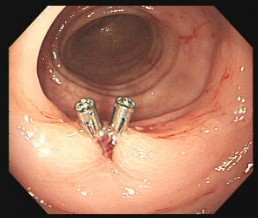

行结肠息肉EMR术+钛铗夹闭止血术,术后患者表示对此次治疗非常满意。